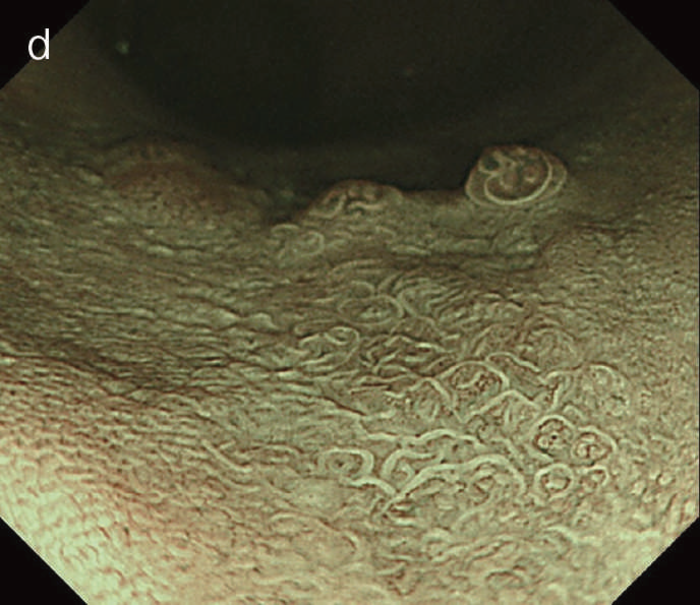

- 白色光像:直腸(下部直腸)に色調変化は乏しく,微小な隆起を複数認めた。背景粘膜は寛解期にあった。

- NBI非拡大像:Brownishな領域が明らかとなった。

- 色素内視鏡像:病変辺縁が明瞭な微小な隆起を複数伴う表面平坦型病変。

- NBI拡大像:口径整でらせん状の微小血管と絨毛状の表面構造を認めた。

- pit pattern像:小型の類円形,管状pitを認めた。